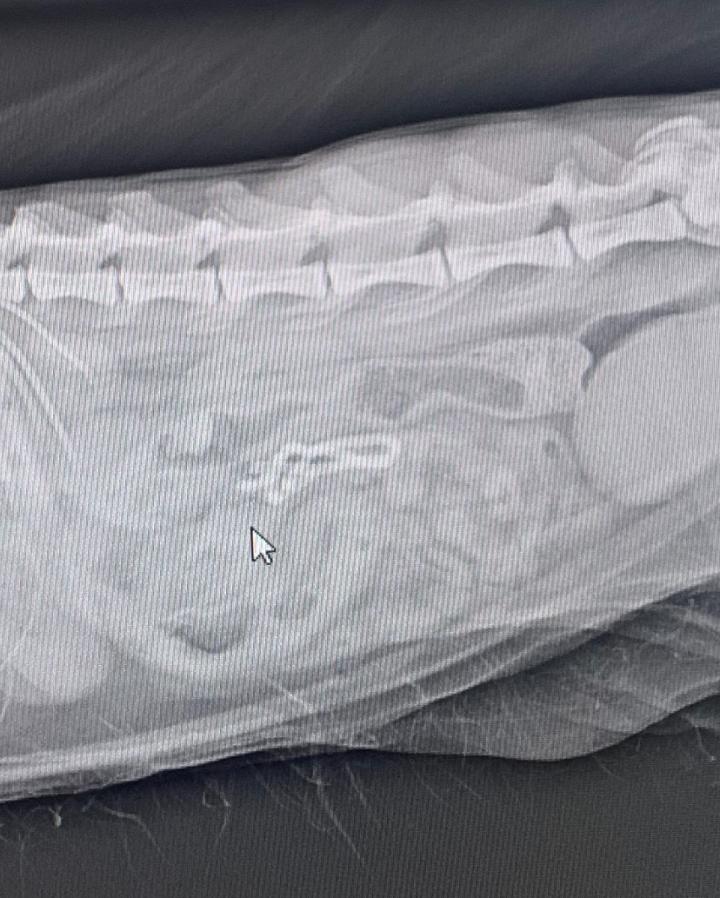

何も食べてない割に胃が張ってるね。これは誤飲かなぁ…とレントゲン撮影。バッチリ長細い何かが腸に写ってます😨

腸を動かし便で出てくれればいいけど…と点滴開始。一向に出てくる気配なし。入院となりました。